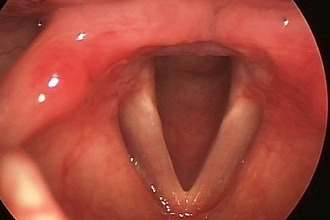

Если в процесс вовлекается гортань, к вышеописанным симптомам добавляются признаки поражения голосовых связок. У пациента может изменяться тембр голоса, появляться осиплость, а в тяжелых случаях голос может стать беззвучным. Перенапряжение голосовых связок также может способствовать их поражению. Острый ларингит может развиться из-за резкого крика или длительного напряжения голосового аппарата у певцов и преподавателей.

Что такое синдром раздраженной гортани (ИЛС)? В ИЛС гортань (голосовой ящик) становится очень чувствительной к раздражителям, приводящим к эпизодам ненужного и контрпродуктивного закрытия голосовой складки (PVFM и ларингоспазм). Некоторые общие стимулы включают сильные запахи, холодный воздух, разговоры.